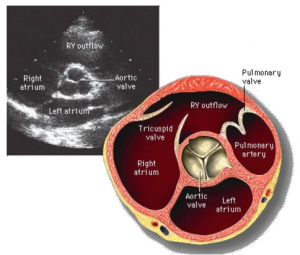

Echo en tekening van een patient met een normale tricuspide aotaklep

Video 3 van een patient met een normale aortaklep en vergroot linkeratrium

Figuur 7: patient met een normale aortaklep en vergroot linkeratrium